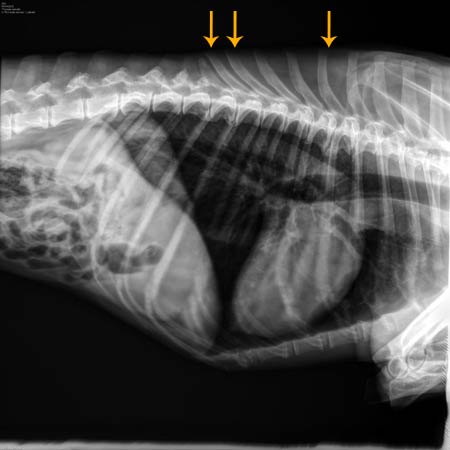

![]() Ter hoogte van de pijlen is in de rug spondylose zichtbaar. |